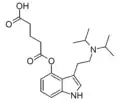

| FT-104 | artificial | 4-OCO(CH2)3COOH | CH(CH3)2 | CH(CH3)2 | 4-glutaryloxy-N,N-diisopropyltryptamine | |